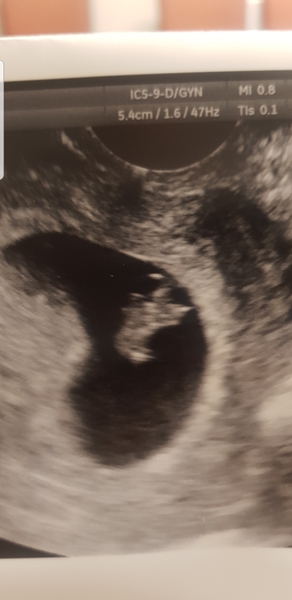

Hi all, got my scan today and all well! Good strong heartbeat and measuring bang on! So edd 4th august! Had my appointment with my consultant after and she's happy, she said that the rate of miscarraige comes right down once there is a hb. So booked in for my next scan in 3 weeks time 🤗 feel like a weight has been lifted and i can enjoy my xmas now!

@Chocolate89 OMG your baby is beautiful 😍😍😍😍😍🎉🎉🎉🎉

Lovely scan pic @Chocolate89 - congrats!

Oh and wow @chocolate89 Congratulations lovely xx

Wow @@chocolate89 that a wondeful pic! Please may I ask how many weeks you are and size of bean Grin. If you don't mind sharing..? No worries if not